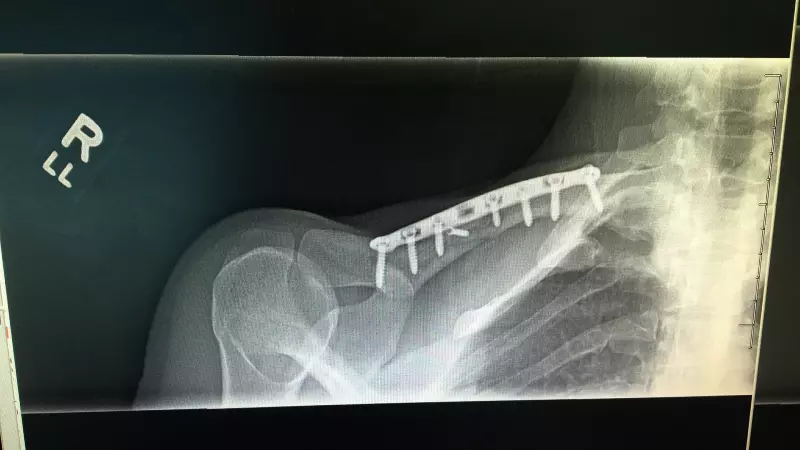

When the wreckage began to clear, some of the affected racers gingerly got back on their bicycles and finished that last mile. Others cleared to the side of the road to tend to more serious injuries. Kathryn was sent into seizures. She had broken her clavicle, suffered two skull fractures (right temporal and sphenoid bones), and endured a severe concussion from the coup-contrecoup brain injury, as she would later be told. Kathryn could only lay helpless while the chaos of the scene spun around her.